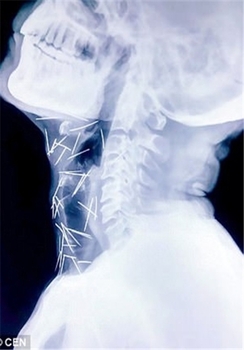

این مرد هندوستانی که «بادریلال مینا» نام دارد و در ایالت راجستان زندگی میکند، 75 سوزن در گردن، دستها و پاهایش وجود داشت.

بررسیها نشان داد حداقل 40 سوزن تنها در گلوی وی فرو رفته است که علت آن همچنان نامشخص است.